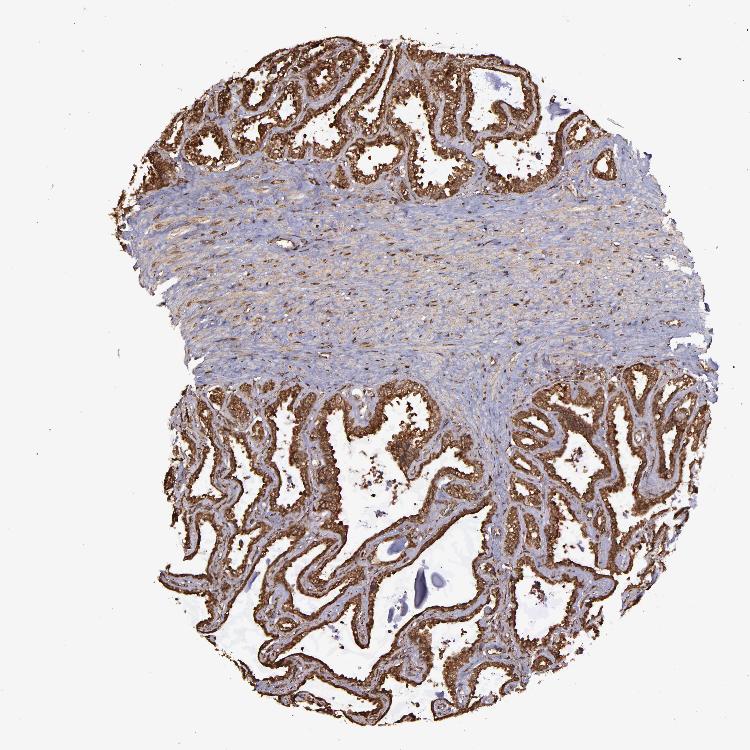

TISSUE PRIMARY DATA SEMINAL VESICLE Show tissue menu

Seminal vesicle

SEMINAL VESICLE - Antibody stainingi

Antibody staining in the annotated cell types in the current human tissue is reported as not detected, low, medium, or high, based on conventional immunohistochemistry profiling in selected tissues. This score is based on the combination of the staining intensity and fraction of stained cells.

Each image is clickable and will lead to virtual microscopy that enables deeper exploration of all samples and also displays staining intensity scores, fraction scores and subcellular localization as well as patient and tissue information for each sample.

Antibody HPA001619Antibody HPA002078

Glandular cells MediumHigh